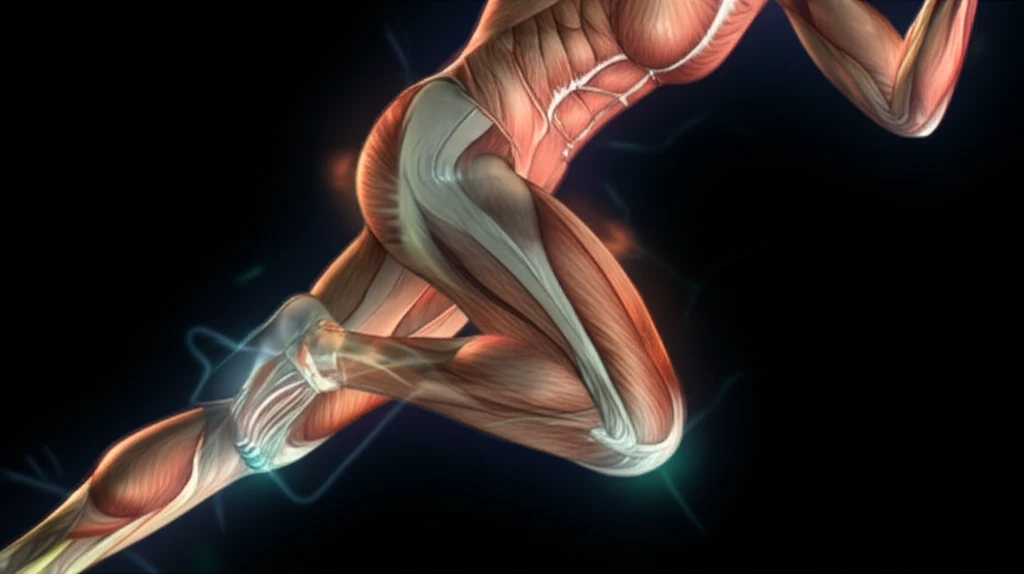

Anterior cruciate ligament (ACL) ruptures can have lasting effects, preventing many from returning to their previous activity levels and increasing the risk of osteoarthritis. Even with surgery or conservative treatment, individuals often struggle to regain full function, with altered neuromuscular patterns persisting years after the initial injury.

Research has shown that those with ACL reconstructions (ACLR) or ACL deficiencies (ACLD) tend to activate their leg muscles earlier than healthy individuals. However, the impact of fatigue on these muscle activation patterns has remained unclear – until now.

The study compared muscle activity patterns in three groups: those with ACLR, those with ACLD, and a control group of healthy individuals. Participants performed repetitive double-leg squats and drop landings to induce fatigue, while researchers measured muscle activity using electromyography (EMG).

- Timing Matters for ACLR: After becoming fatigued, individuals with ACLR showed earlier activation of the medial hamstring, lateral hamstring, and vastus lateralis muscles compared to the control group. This suggests they rely on preemptive muscle activation to stabilize the knee joint.

- Quadriceps Power in ACLD: Those with ACLD exhibited greater activity in the vastus medialis muscle compared to both the ACLR and control groups after fatigue. This indicates an increased reliance on the quadriceps to maintain knee stability.

- Gastrocnemius Decline: Fatigue led to decreased activity in the lateral gastrocnemius muscle in both the ACLD and control groups, suggesting a potential shift in stabilization strategies.